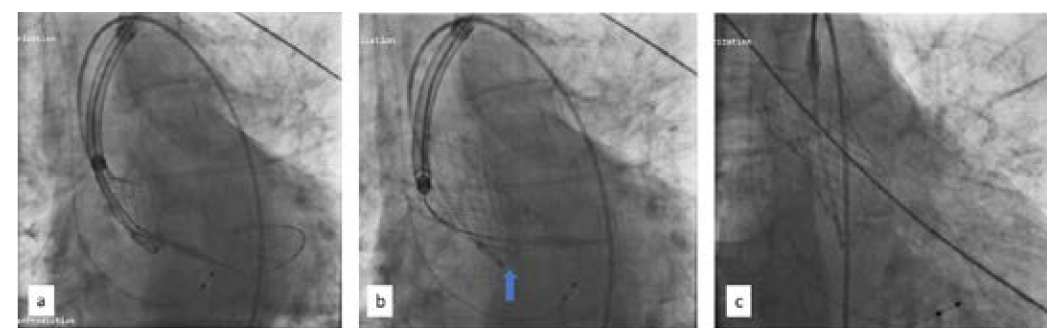

There was no coronary obstruction, and the patient was hemodynamically stable. Using a bioptome (Cordis), the valve was pulled high in the aorta, leaving it just proximal to the origin of the brachiocephalic artery (Figure 4). The aortic valve was recrossed and another 26-mm Evolut R self-expanding valve was deployed successfully (Figure 5).